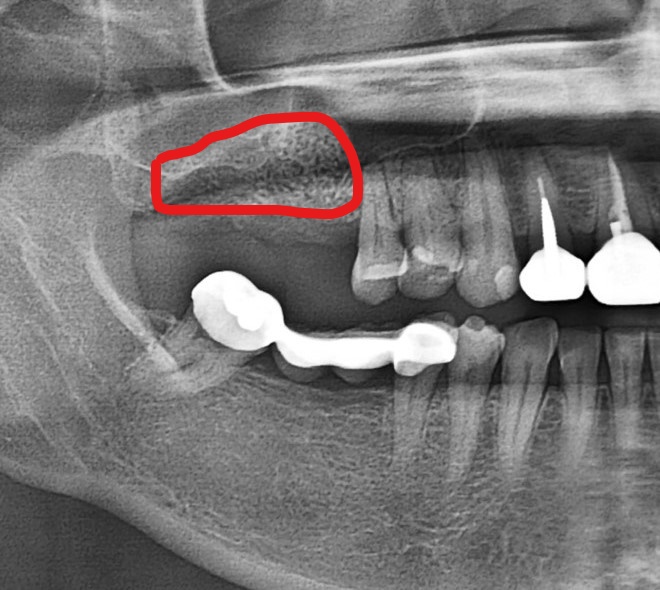

- 術 後

經醫生判斷下,在植牙手術前先做鼻竇增高補骨手術,讓骨頭條件變好,大大增加之後植牙手術成功率及穩定度。